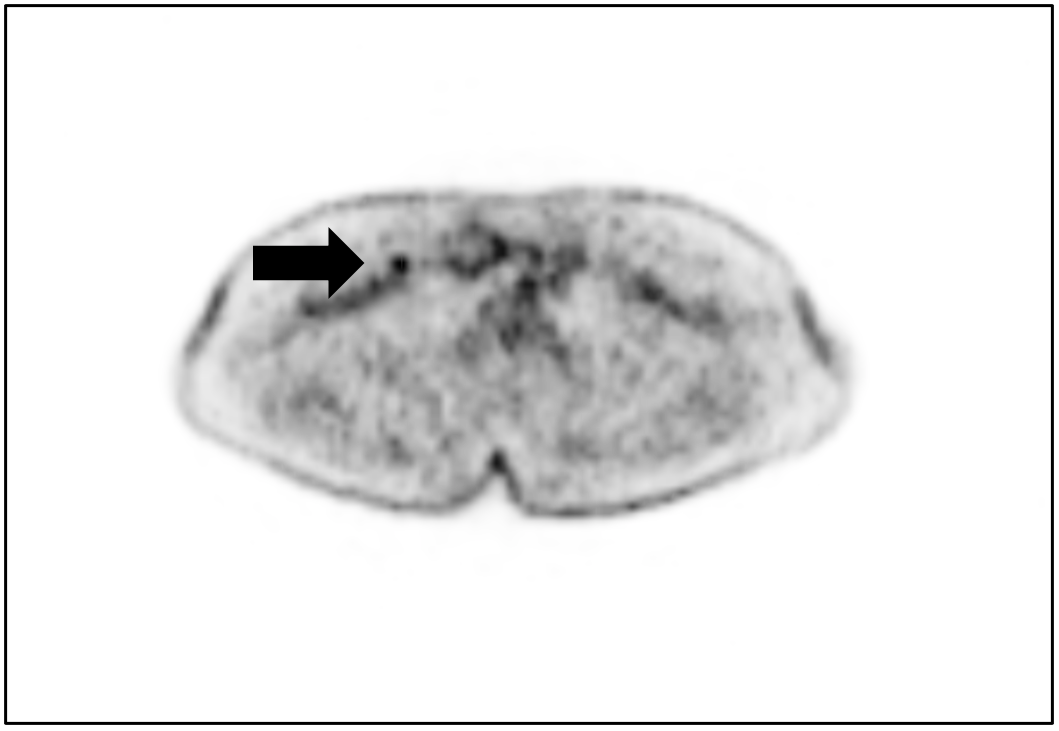

Owing to the aggressive cancer in a young patient, a staging PET/CT study was performed which showed a small but metabolically active lymph node in the right supraclavicular fossa. An US of the supraclavicular fossa revealed several small volume nodes. The most prominent 10 x 4 mm node had a normal architecture but with only mild cortical thickening. Power Doppler imaging (PDI) and color Doppler imaging (CDI) showed feeding vessels but otherwise no suspicious features. However, on using Superb Microvascular Imaging monochrome (SMI), this revealed abnormal peripheral vascularity which was best depicted in the monochrome mode. This feature made the node suspicious for malignancy and corresponded to the FDG avid node on the PET study. Subsequent fine needle aspirate of the right supraclavicular node confirmed metastatic disease.

Longitudinal ultrasound of right supraclavicular fossa showed a small 10 x 4 mm lymph node in the right supraclavicular fossa (SCF) with mild cortical thickening. SMI revealed abnormal peripheral vascularity which made it suspicious for metastatic infiltration and most likely represented the metabolically active SCF node on the recent PET imaging.

Clinical perspective: PDI and CDI ultrasound showed relatively normal vascularity in the SCF Lymph node, however, SMI, particularly monochrome mode, outlined clearly the abnormal peripheral vascularity which allowed FNA of the correct “small” node which was FDG avid on the PET study . A recent study has shown SMI yields more detailed information about nodal vessel when compared to PDUS and can be useful in differentiating between malignant and benign lymph nodes.